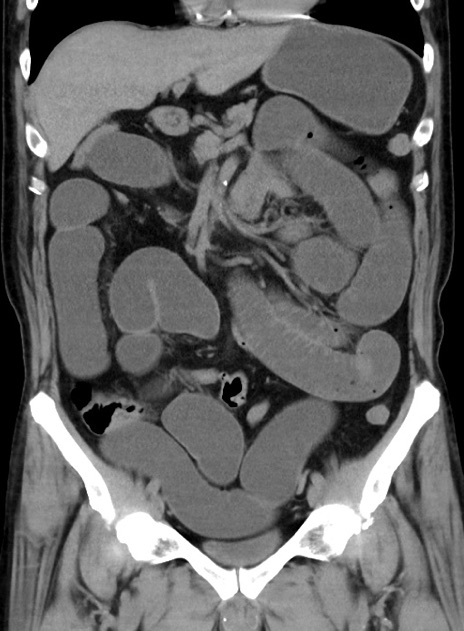

症例38(冠状断像)

【症例】70歳代 男性

【主訴】腹痛・嘔吐

【現病歴】昨晩より、嘔吐・腹痛あり。今朝になっても嘔吐あり。来院。

【既往歴】心臓バイパス手術、開腹胆摘、腸閉塞

【身体所見】BP 107/71mmHg、HR 116/min、腹部:平坦、軟、下腹部に軽度圧痛あり。反跳痛なし。

【データ】WBC 15100、CRP 0.32

横断像